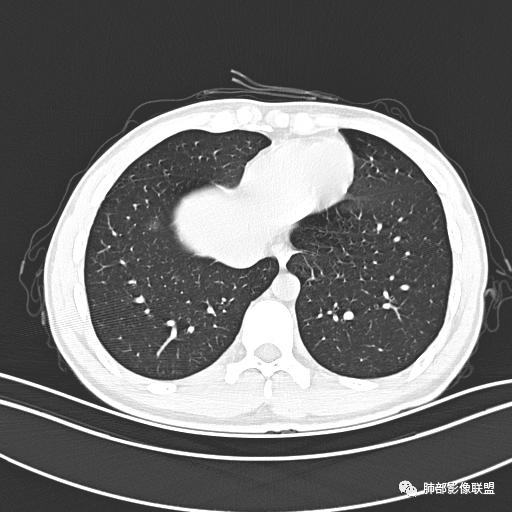

男,19岁

主  诉:发热、全身皮疹2天。

现病史:患者源于2天前受凉后出现发热,最高体温为38.5℃,且颜面部出现少量皮疹,无鼻塞、流涕、咳嗽、咳痰,未在意而未作特殊处理,次日全身皮疹逐渐增多至全身,伴轻度瘙痒,在当地卫生所给予抗病毒、抗感染治疗(具体用药不详)体温有所下降,但皮疹无明显消退,无腹痛、头痛,食欲无明显减退,为进一步诊治,遂于今日急来我院求治,患者目前精神尚可,体力正常,食欲正常,睡眠正常,体重无明显变化,大便正常,排尿正常。

小强:青年,发热,皮疹;双肺散在结节,周围磨玻璃,点晕征,疱疹病毒感染,鉴别荚膜组织胞浆菌,结核。 大雄:青年,急性起病,发热伴全身皮疹2天,抗病毒治疗体温有下降。双肺随机分布大小不等类圆结节,“点晕征”。考虑水痘-疱疹病毒(VZV)血播询问接触史,查体皮疹分布以及形态基本可诊断。 王开金江津中心医院呼吸科:青年男性,起病急,病程短,以发热,皮疹为首发症状,感染指标以单核细胞升高为主,胸部ct双肺多发结界,周围有晕,点晕表现,随机分布,同意於老师意见,水痘疱疹病毒血流感染累及肺。 王秀仙:双肺多发大小不等结节,周围有晕,边缘模糊,呈点晕征表现。青年,急性起病,发热伴全身皮疹2天,抗病毒治疗体温有下降。考虑疱疹病毒。鉴别荚膜组织胞浆菌。 傅昌瑜:19岁男性,发热、全身皮疹2天,单核细胞增高,双肺多发结节,结节边缘见边界不清磨玻璃影。点晕征+发热、全身皮疹+单核细胞增高——考虑水痘-带状疱疹病毒肺炎。 一切∮随缘:年轻男性,发热,皮疹两天,实验室,CRP,PCT增高,影像:双肺多发散在磨玻璃结节,边界欠清,大小不等,呈点晕征改变,以血管束周围分布为主,局部血管束略增粗,其它无明显改变,考虑:1:病毒性肺炎(水痘疱疹病毒?不知道皮肤有无改变)2:真菌(组织胞浆菌,血管侵袭性肺曲霉)3:GPA4:寄生虫(实验室没有看到嗜酸细胞增高) 赵山河:双肺散在结节,周围有晕,边缘模糊,呈点晕征表现。青年,急性起病,发热伴全身皮疹2天,抗病毒治疗体温有下降。考虑水痘—疱疹病毒感染。洪桥爱:青年男性,发热、皮疹2天,伴瘙痒,皮疹于面部首发,之后进展至全身,虽然没有对皮疹进行描述,但是从出疹时间及皮疹进展情况,伴瘙痒,应该就是个水痘患者;CT提示双肺随机分布结节影,部分结节伴有边界不清晕征,考虑水痘血播肺。 刘强:年轻男性,急性起病,皮疹,发热,抗感染治疗体温下降,说明有效。影像表现为散在点晕征,感染类疾病谱(疱疹病毒,真菌,结核),结合年龄,皮肤皮疹,考虑水痘-疱疹病毒性肺炎。 小兜:男性,19岁,发热皮疹两天,颜面部至全身,CRP,降钙素及单核增高。CT示双肺散在小结节,周围伴磨玻璃影,点晕征,考虑为水痘-带状疱疹病毒(varicella-zoster virus,VZV)肺炎 必有路:青年,皮疹+发热+“点晕征”→水痘-疱疹病毒(VZV) 许慧良:青年男性患者,发热、皮疹2天,体温最高38.5℃,第3天皮疹扩展至全身,伴瘙痒,胸部CT:双肺多发随机分布的小结节,结节周边见边界模糊的晕征,考虑水痘病毒感染流心明智:男,19,急性起病,发热伴全身皮疹2天。出疹顺序头→全身,抗病毒有效。胸部CT:两肺多发大小不等类圆形实性小结节影,随机分布,结节周围环绕GGO,边界模糊,呈点晕征。出疹特点是关键,未提示。考虑:血播病毒性肺炎,水痘-疱疹病毒?麻疹?鉴别荚膜组织胞浆菌、TB、血管炎、寄生虫等。 浪迹天涯:病灶多为5-10mm大小结节,结节周围可见磨玻璃样的晕环,常多发,可分布于肺内任何区域,考虑水痘—带状疱疹病肺炎如果短时间内有新的一个区域浸润,更加能说明,